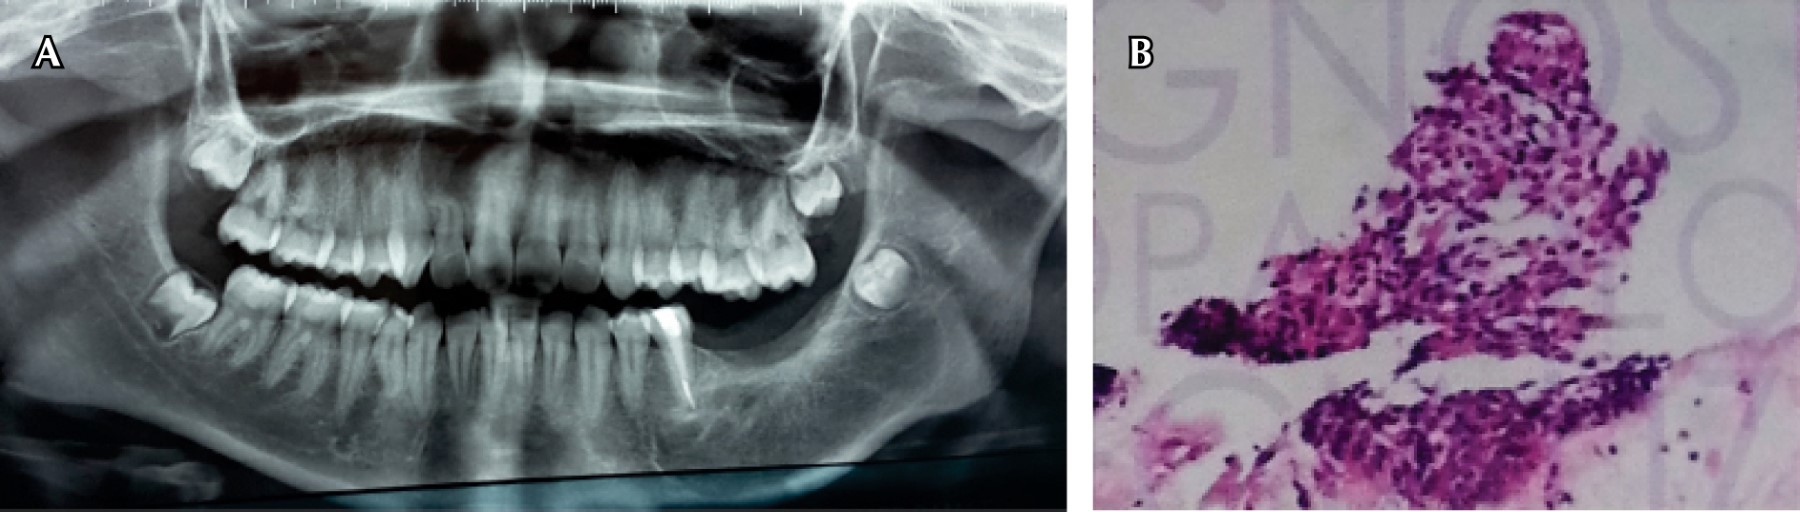

Se realizó revisión y segundo tiempo quirúrgico para llevar a cabo la remoción del tercer molar inferior izquierdo y segundo premolar inferior izquierdo. Los resultados de la biopsia fueron: fragmento de tejido de consistencia firme, de forma irregular y de superficies anfractuosas, con bordes espiculados, además, en la superficie se encontraron restos de tejido fibroso de color café claro, hemorrágico, en conjunto miden 1.5 × 1 cm.

En la descripción histológica se encontró que los fragmentos de tejido mostraron predominantemente un estroma fusocelular donde proliferaron numerosas células de aspecto fibroblástico y que descansaron sobre una matriz de finas bandas de colágeno. El componente más importante de la lesión fue un estroma fusocelular que no mostró atipia citológica ni actividad mitótica anormal. En 2% del tejido revisado, y principalmente localizado hacia la periferia, se encontraron escasas islas pequeñas y compactas de células cuya morfología fue compatible con epitelio odontogénico (Figura 3).